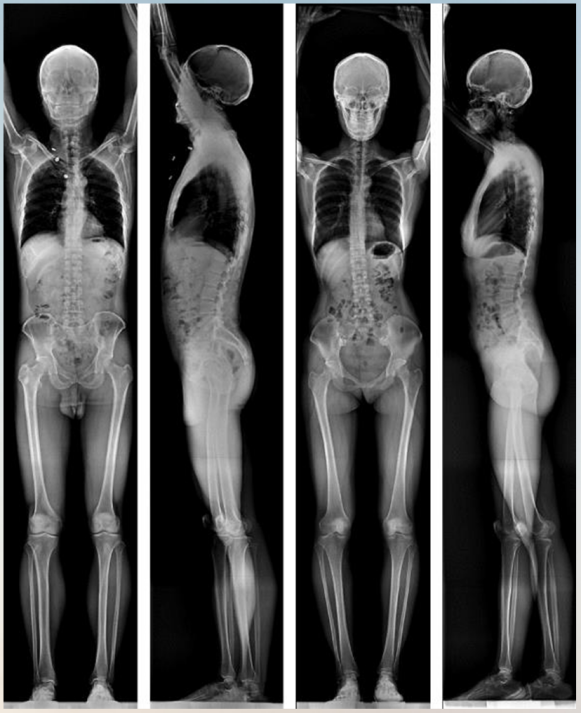

上海涛影医疗公司研发国内唯一的双平面全长X光成像设备

双平面全长影像范例,包含正位与侧位图像